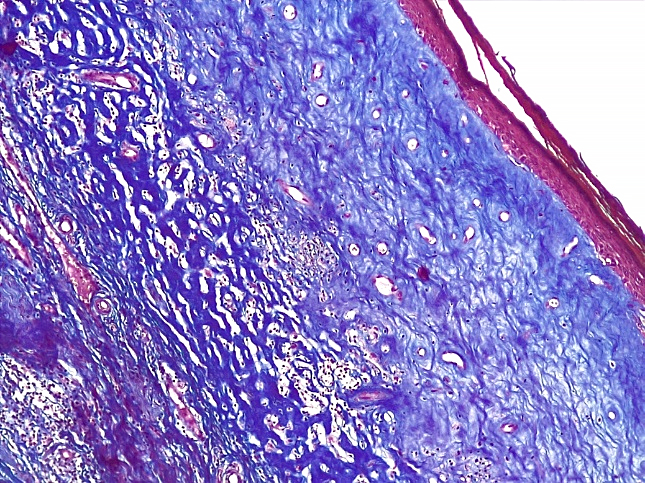

При проведении морфологического исследования тканей вульвы пациенток со склероатрофическим вариантом течения СЛВ также отмечалась резкая атрофия кожи за счет клеток эпидермиса и дермы, уменьшение клеточных слоев эпидермиса от 2–3 до 4–5 с участками повышенного ороговения (гипрекератоз). Количество базального слоя было снижено в разных случаях от 2–3 до 5–6 клеток в 1 мкм, что указывало на снижение функционального резерва эпидермиса. В случае длительного течения заболевания клетки базального слоя имели признаки дистрофии. В поверхностных слоях дермы отмечался фиброз с отложением масс гиалина, а также редукция кровеносных сосудов мелкого калибра, окруженных клеточным воспалительным инфильтратом из лимфоцитов и макрофагов (рис. 14–17).

Рис.15. Склероатрофический вариант СЛ. Резкая атрофия и дистрофия клеток эпидермиса, выраженный фиброз и гиалиноз поверхностных слоев дермы с редукцией сосудов микроциркуляторного русла, развитием фиброзной ткани в глубоких слоях дермы (ШИК-реакция по Хочкиссу, х100)

Fig.15. Scleroatrophic variant of SL. Sharp atrophy and dystrophy of epidermal cells, pronounced fibrosis and hyalinosis of the superficial layers of the dermis with reduction of microcirculatory vessels, development of fibrous tissue in the deep layers of the dermis (CHIC-Hotchkiss reaction, x 100)